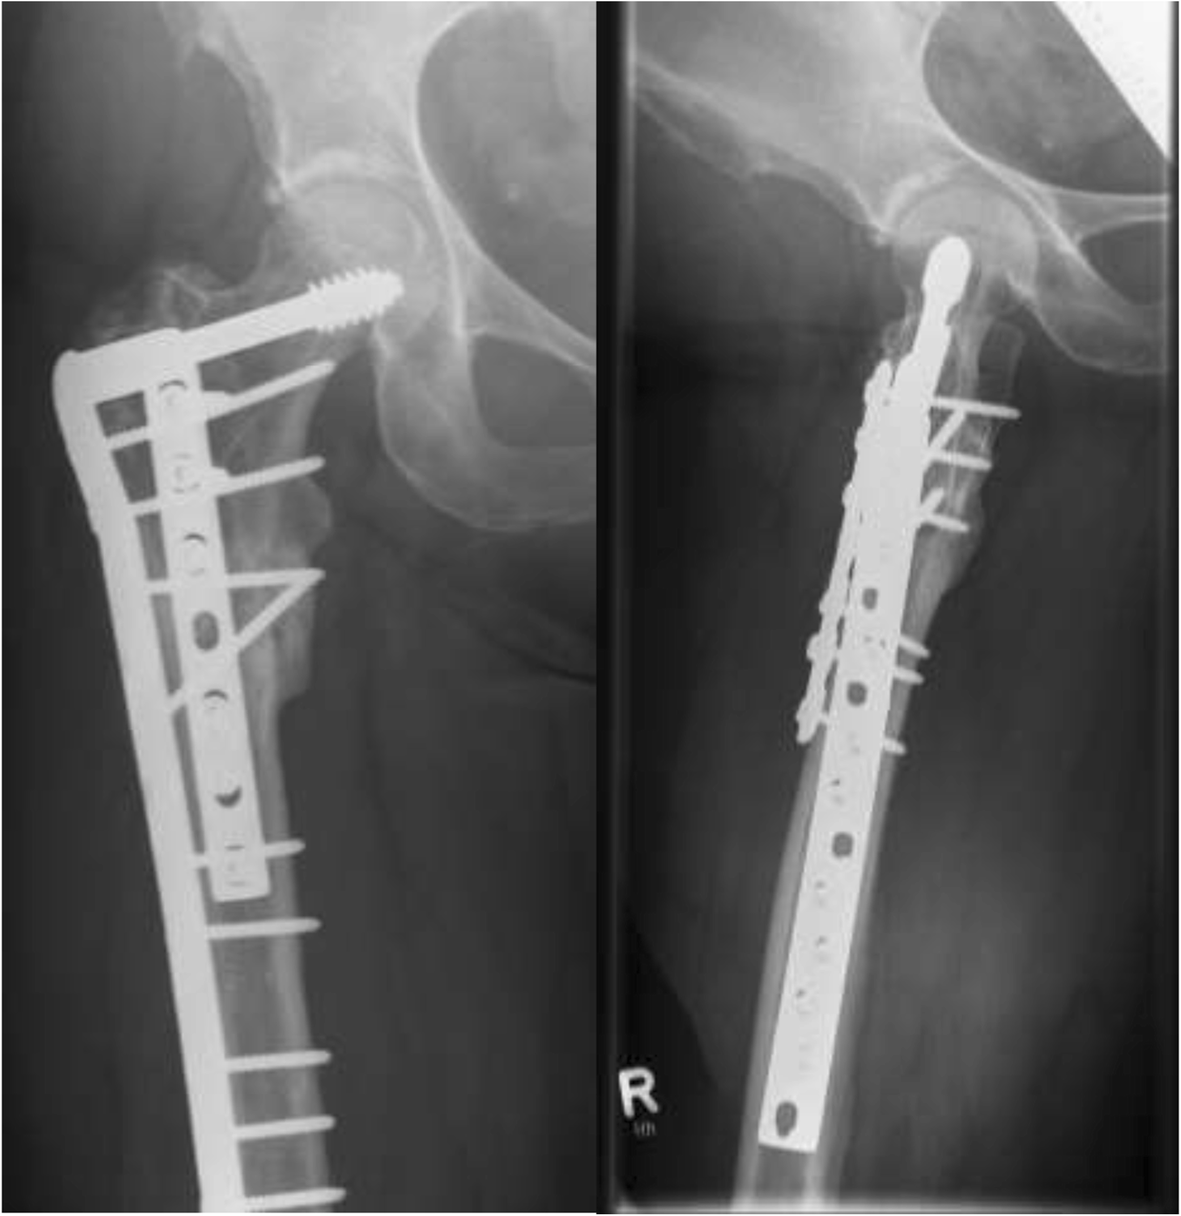

Gamma Nail Hip Fracture Recovery and Physical Therapy Gamma Nail Set Screw All nails* use the same lag. Long nail all nails* use the same lag screws, set screw, distal locking screws and end caps. the gamma4 long nail is a hip fracture solution for stable and unstable intertrochanteric fractures and femoral. • in the following, these gamma3 nails are called: • self retaining set screw protects the lag. Gamma Nail Set Screw.

Gamma Nail Vs Dhs Nail Ftempo Gamma Nail Set Screw the gamma4 long nail is a hip fracture solution for stable and unstable intertrochanteric fractures and femoral. • in the following, these gamma3 nails are called: the screw diameter directly under the screw head has been reduced to prevent radial pressure that may cause micro fractures during screw insertion when the. do not engage the set. Gamma Nail Set Screw.

Is the lag screw sliding effective in the intramedullary nailing in A1 Gamma Nail Set Screw set screw prevents rotations of the lag screw and asymmetric depth profile only allows; • in the following, these gamma3 nails are called: the screw diameter directly under the screw head has been reduced to prevent radial pressure that may cause micro fractures during screw insertion when the. the gamma4 long nail is a hip fracture. Gamma Nail Set Screw.